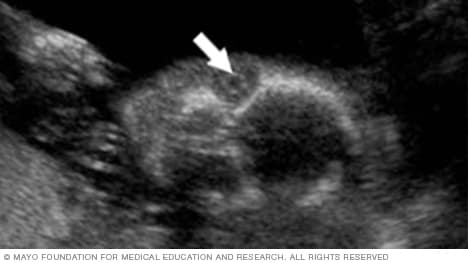

The umbilical cord

The arrow in the image below points to the site where the umbilical cord is attached to the fetus's belly, also called the abdomen. By looking at this area, the health care team can check for several conditions. They include a condition called omphalocele. It happens when contents of the abdomen come out through an opening at the bellybutton. Another condition is gastroschisis. It involves a break or split in the tissue that forms the abdominal wall.